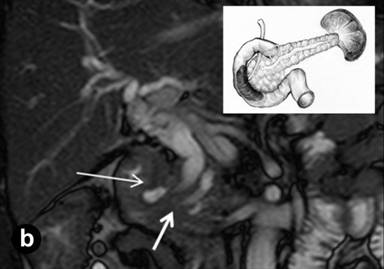

A 43-year-old man with abdominal pain of a one year duration, nausea, vomiting, weight loss and intermittent jaundice was referred to the Hospital of the Russian Federal Security Service, Moscow, Russia, with a clinical diagnosis of chronic pancreatitis. The patient had a history of previous extensive small bowel resection; one year previously he had been operated on for acute pancreatitis with abdominal draining and a cholecystectomy. The epigastrium was mildly sensitive on physical examination. The laboratory findings were normal, except for a slight increase in the bilirubin level (40 µmol/L; reference range: 3.5-19.0 µmol/L). Abdominal US showed diffuse changes of the liver and pancreas. On computed tomography (Figure 6) and magnetic resonance imaging (Figure 7), a thick-walled cystic lesion 4x4.5 cm which had infiltrated the medial wall of the second part of the duodenum was observed against the background of the minimally changed pancreatic structure with pancreatic and common bile duct dilation,. Endosonography revealed a solid and septated cystic lesion mainly located in the submucosa of the narrowed second portion of the duodenal wall.

Figure 7. Magnetic resonance imaging (Case #2). (a.) Magnetic resonance cholangiopancreatography; (b.) Balanced turbo field echo (B-TFE). A septated cyst is located in the medial wall of the second part of the duodenum (long arrows) causing biliary and pancreatic hypertension (large arrow). Stenosis of the terminal parts of the common and the main pancreatic ducts (short white arrow). Scheme of the lesion and unaffected pancreas is in the upper right corner. |

|